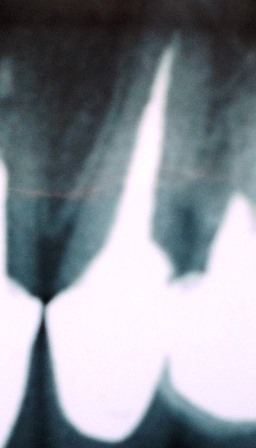

Popularmente conhecida como tratamento de canal, consiste na remoção do nervo e descontaminação das paredes internas e obturação da raiz.

Clique na imagem para ampliar: